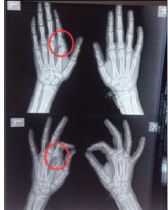

Eight-Year Neglected Pediatric Kaplan’s MCP Dislocation Following Childhood Trauma Managed by Volar Open Reduction: A Case Report

Siddhant Pundalik Pol , Pankaj Pundlik Pawar , Sudhir Sharan , Ashwin Joshi , Priyanka Tanaji Ahire , Suresh Kalal

………………………………p.220-224